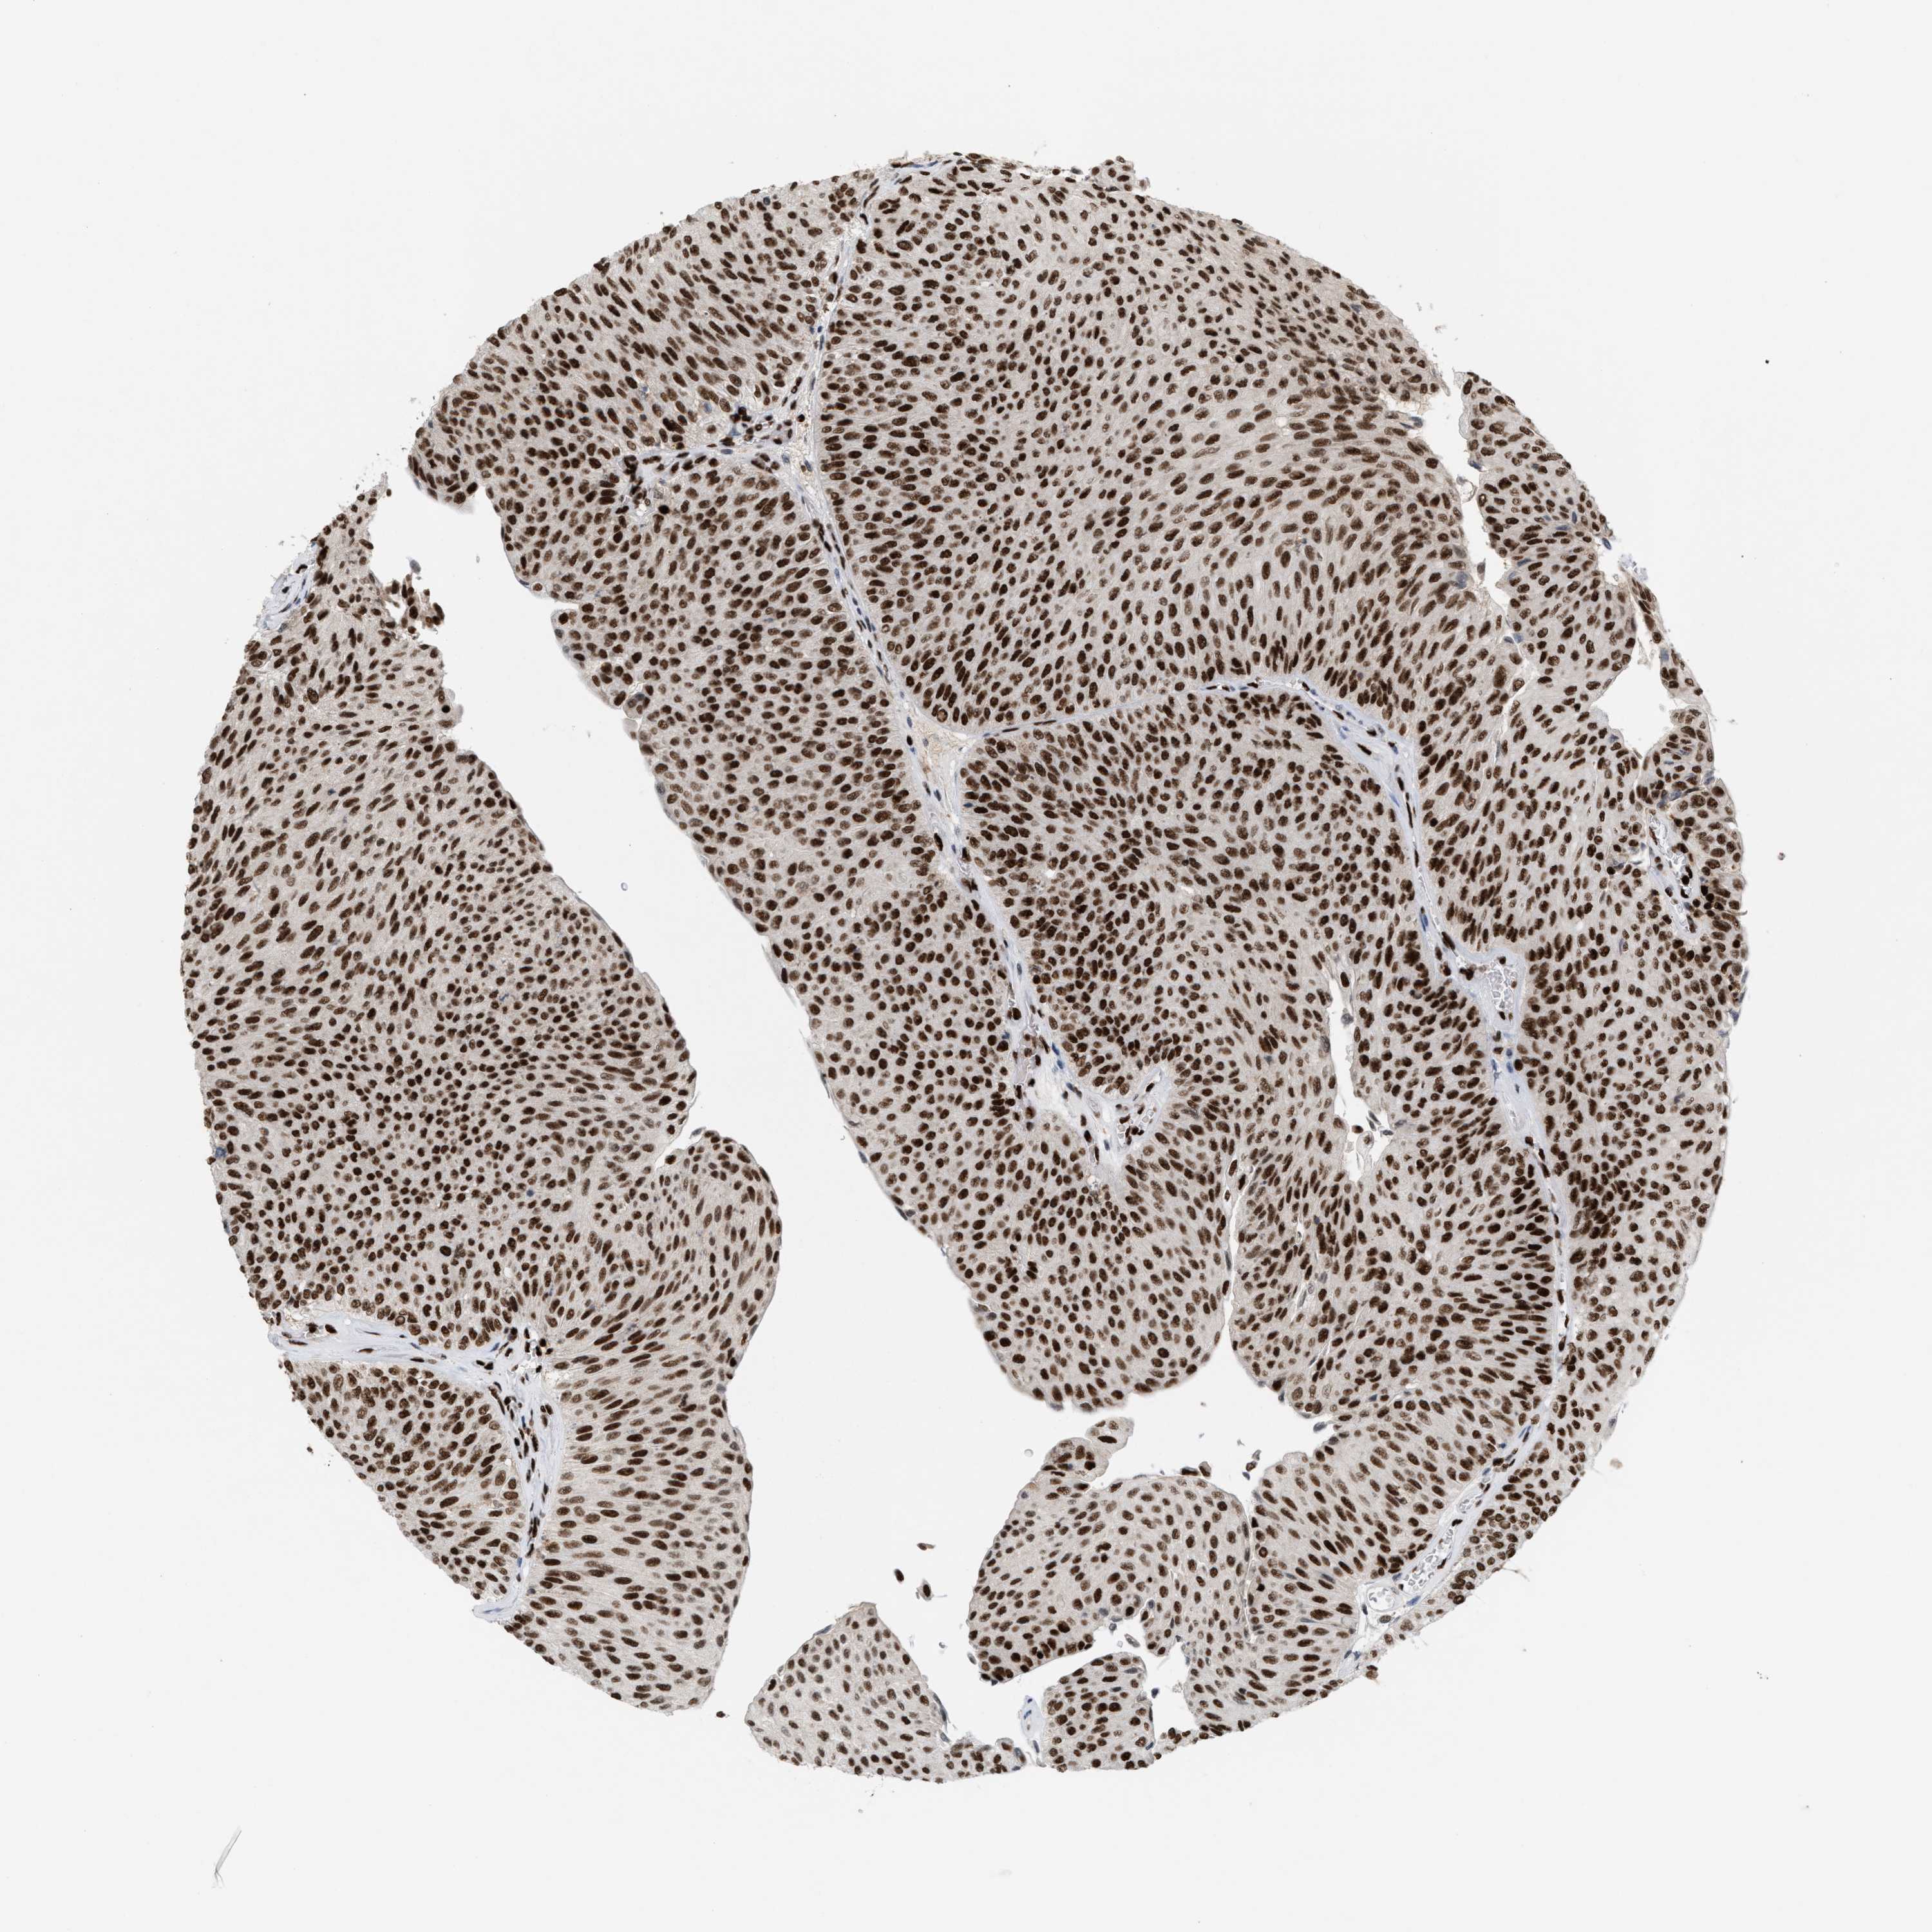

UROTHELIAL CANCER - Protein expressioni

A mouse-over function shows sample information and annotation data. Click on an image to view it in a full screen mode. Samples can be filtered based on level of antibody staining by selecting one or several of the following categories: high, medium, low and not detected. The assay and annotation is described here.

Antibody stainingi

Antibody staining in the annotated cell types in the current human tissue is reported as not detected, low, medium, or high, based on conventional immunohistochemistry profiling in selected tissues. This score is based on the combination of the staining intensity and fraction of stained cells.

Each image is clickable and will lead to virtual microscopy that enables deeper exploration of all samples and also displays staining intensity scores, fraction scores and subcellular localization as well as patient and tissue information for each sample.

Antibody HPA024457

Urothelial carcinoma, Low grade

Urothelial carcinoma, High grade